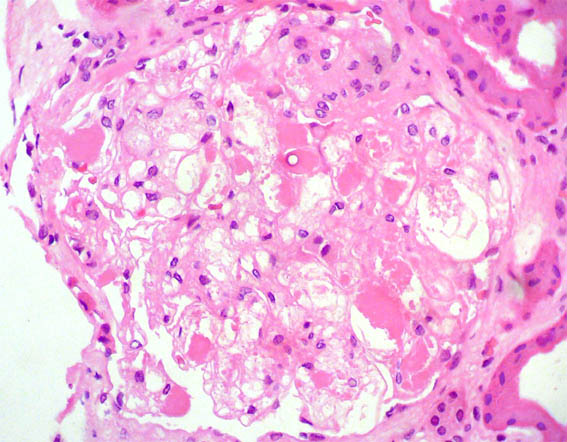

Figure 2.

H&E, X400.